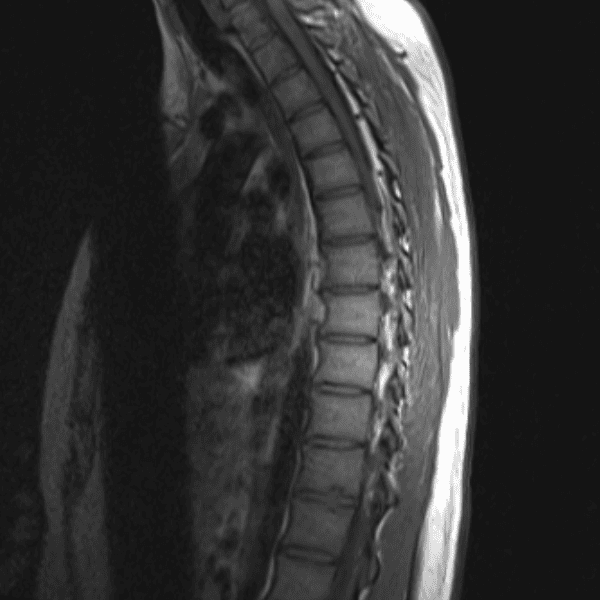

Simulates call by including subtle or difficult cases and some normals.

35 cases